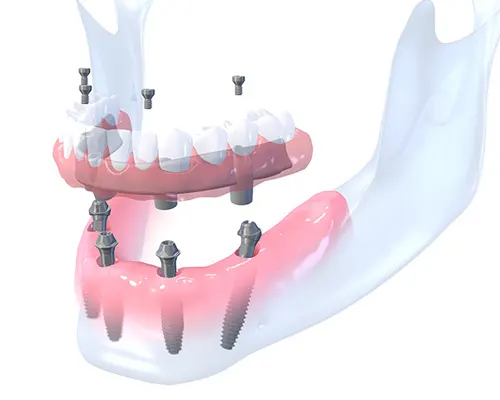

The All-on-4 dental implant treatment has been developed to maximize the use of available bone on anterior jaw and to allow for Immediate Function™ by the uses tilting posterior implants.

With the all-on-4 dental implant technique, teeth is extraction and the implant post placed during the same surgical visit. A fixed acrylic bridge is fabricated and functioning within 1 to 2 days after surgery. The timeline for all-on-4 dental implants is thus completed within one trip. Patients are able to opt to have the acrylic bridge converted into a porcelain bridge at a later stage.